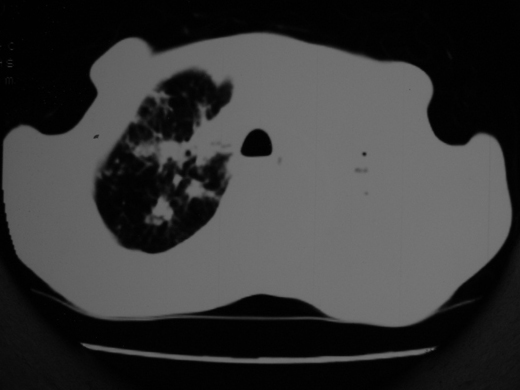

右肺多发片絮状结节状及时条索状影,左上肺实变,内可见虫蚀样空洞及支气管气象,左下肺片状及球形病灶,及胸腔积液征象,双肺病灶内多发钙化影,结合病史,考虑双肺继发型肺结核,左胸腔积液

右肺多发片絮状结节状及时条索状影,左上肺实变,内可见虫蚀样空洞及支气管气象,左下肺片状及球形病灶,及胸腔积液征象,双肺病灶内多发钙化影,上纵隔向左侧移位,结合病史,考虑双肺继发型肺结核,左胸腔积液。

右肺多发片絮状、结节状及条索状影,左上肺实变,内可见虫蚀样空洞及支气管气象,左下肺片状及球形病灶,有胸腔积液征象,双肺病灶内多发钙化影,上纵隔向左侧移位,结合病史,考虑双肺继发型肺结核,左胸腔积液。 建议结合ppd检查或纤支镜检查!

双肺结核,左肺实变。左侧胸腔积液(部分包裹)。

右肺可见大片状、云絮状改变。右肺可见散在类圆形影,以外带多见。左肺实变,其内可见明显支气管走行影。纵隔淋巴结有增大,左侧胸腔积液。考虑1、肺结核;2、肺癌肺转移不除外;3、左侧胸腔积液。